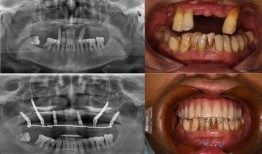

佛山种牙爆料事件最新,揭露行业乱象,患者权益如何保障?

最近佛山那边的种牙事件可是闹得沸沸扬扬的,咱们得好好来聊聊这个话题。你有没有想过,一颗牙齿的种植竟然能引发这么大的波澜?那就让我...